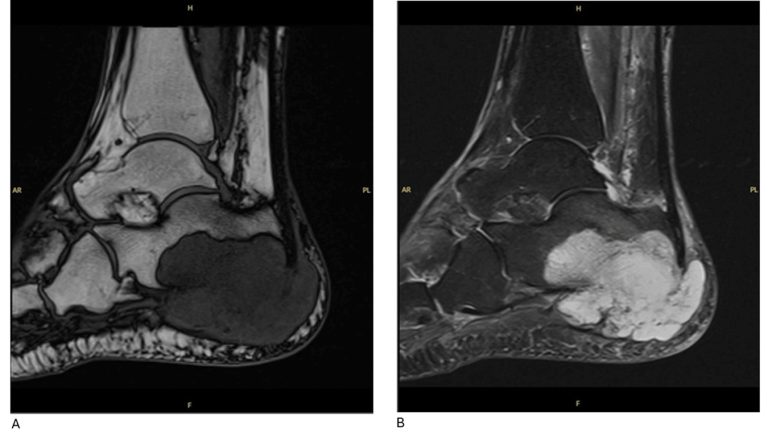

Een 79-jarige vrouw in Engeland had pijn in haar rechtervoet. Haar huisarts diagnosticeerde het als fasciitis plantaris (‘hielspoor’). Maar toen de pijn na twee jaar nog niet was verdwenen, bleek ze kanker te hebben. Haar onderbeen moest worden geamputeerd.